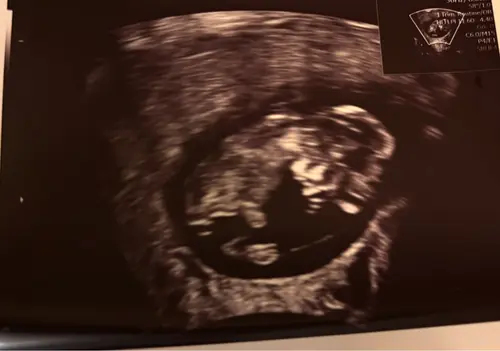

Mijn termijn echo 1-8-26

Hier blijft het 3-8, alles zat goed gelukkig. Op de foto niet te zien, in de echo armpjes en beentjes waren al aan het trappelen.

Paar dagen vooruit gezet, wordt 1-8. Allebei helemaal in orde en lekker druk 🥰

Van 4-8 naar 2-8 gezet. Wat was het leuk om te zien hoeveel het in korte tijd gegroeid is. Zelfs de voetjes en teentjes waren al goed te zien🥹.

Dit is die van vandaag kreeg 2 dagen later aan gegeven dan eerst nu 6-8 uitgerekend

Zo intens spannend, van de eerste echo met 7+2 moeten wachten tot vandaag 11+2. Maar het was het wachten waard en we hebben een super goede 2e echo gehad! ❤️ datum stond al vast ivm icsi 01-08-2026, groei loopt wel 2 dagen voor 🤗🥰

Vandaag een goede termijnecho gehad. Weer 2 dagen naar voren gezet dus nu 11w+2d. Uitgerekende datum staat vast op 2 augustus. 🩵🩷

Ons hummeltje wilde zich niet goed laten zien, dit was maar 1 seconden maar gelukkig gemeten en we zijn weer 5 dagen vooruit gezet. 30/7 uitgerekend ✨

Hier vandaag termijn echo gehad met 10+4, baby word 11 weken gemeten maar omdat ik iui gehad heb blijft de uitgerekende datum 7augustus🥰

Hier termijn echo gehad met 10 +6, alles zag er goed uit!

Termijn echo van 10 +4 ons kindje was 2 weken geleden 8+4 dus echt mooier kan niet! Mooie walnoot hersentjes gezien , er werd nog naar ons gezwaaid door ons kindje en ook het blaasje was al te zien. De verloskundige was onwijs tevreden! En wij ? Wij ZO trots

Hier ook alles goed! De kleine heeft gezwaaid en alles, heel erg leuk! Pak van mijn hart. Nu ga ik de rest van de avond naar dat zwaaitje kijken op repeat 🔁

Hier 9 weken en 1 dag 🥰 mooi kloppend hartje en armen en benen druk aan het bewegen